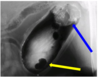

what is this?

Small kidney and abnormal ca

Was ist Das?

IVU

Mis-shapen – fibrotic

Small